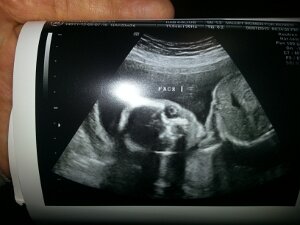

Our Baby

August 7th